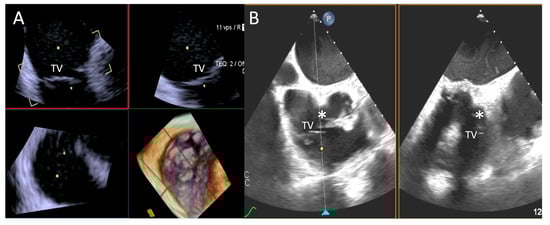

- Step number 7: leaflet insertion.

- Step number 8: evaluation of residual regurgitant jets.